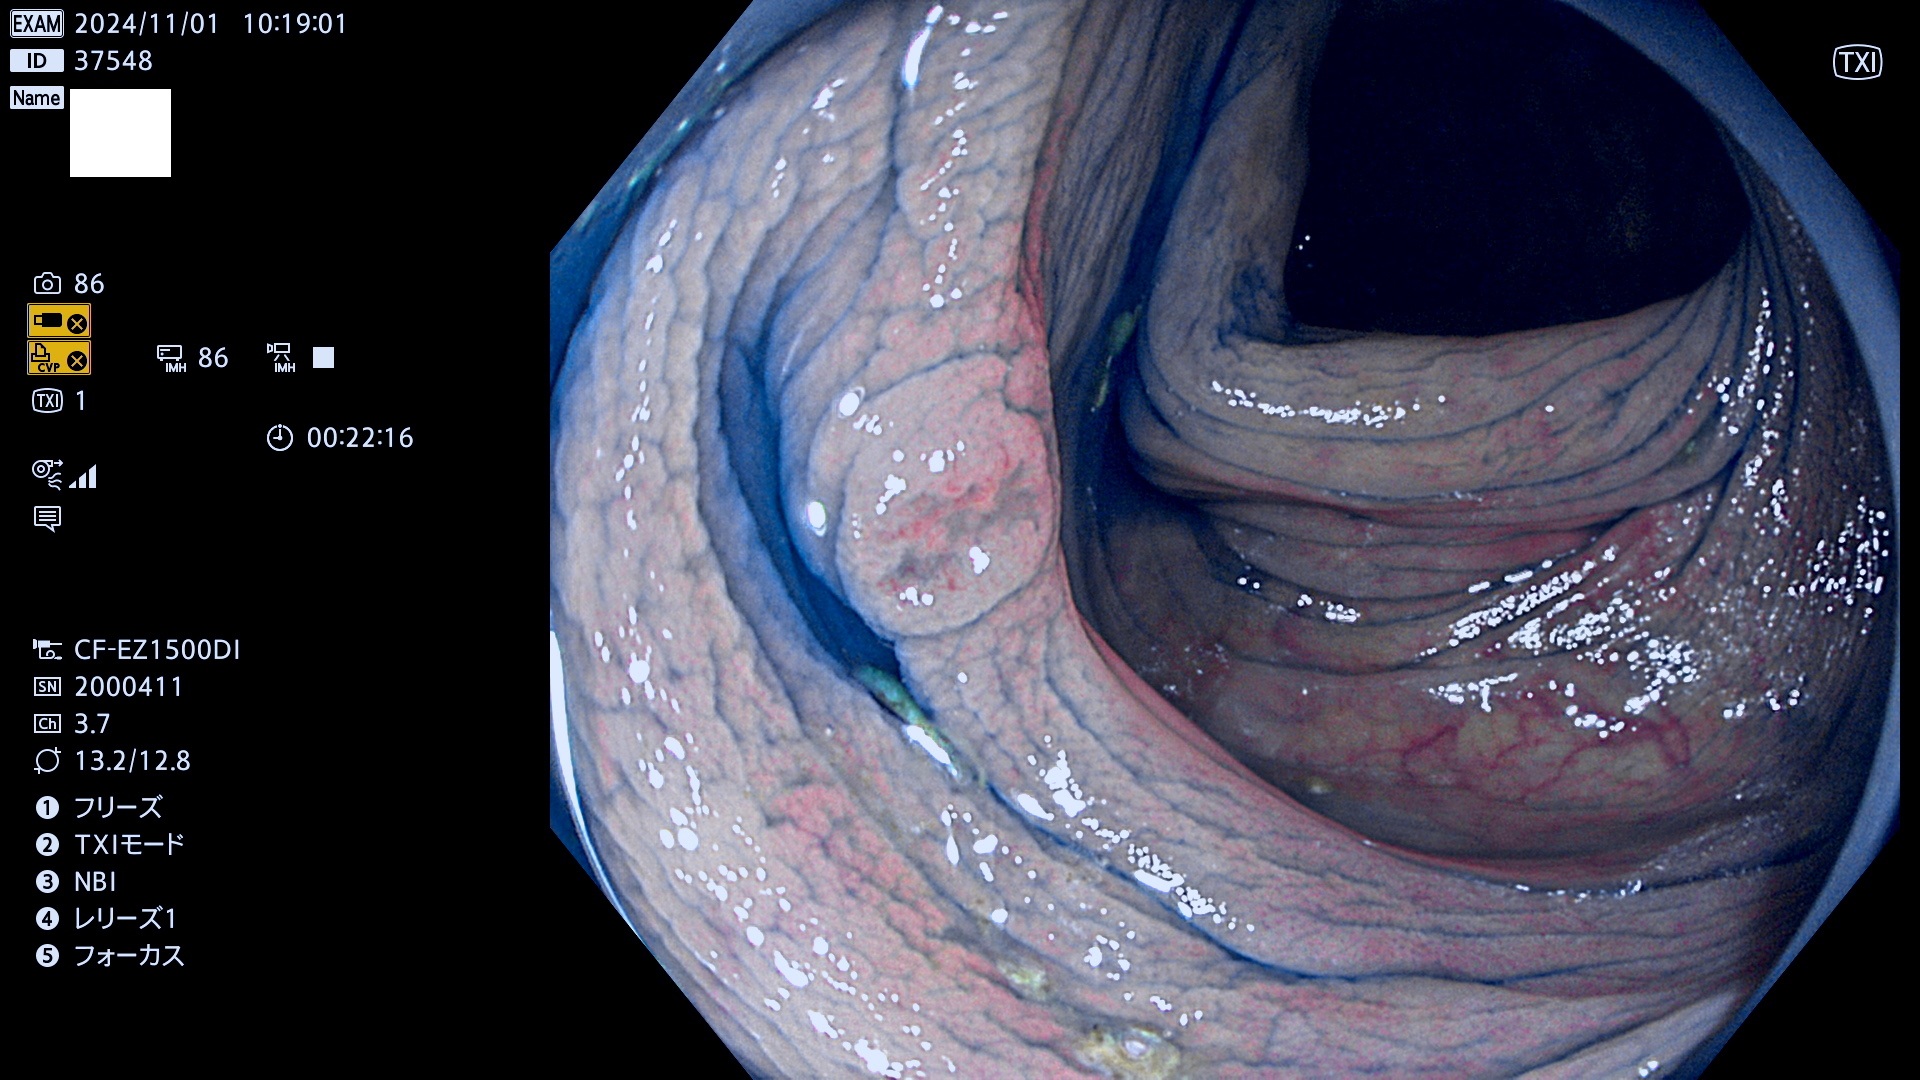

完全に平坦な物をUb、陥凹している物をUcと呼びます。最も発見が難しく危険な病変です。

毎週の検査(木・金・土・日)に発見されたUb、Uc型・腺腫を、その週の日曜の夜にUPし1週間、提示します。

抽出の対象期間 2024年10月31日〜11月3日の4日間(48件の検査)7件 (7/48=15%)